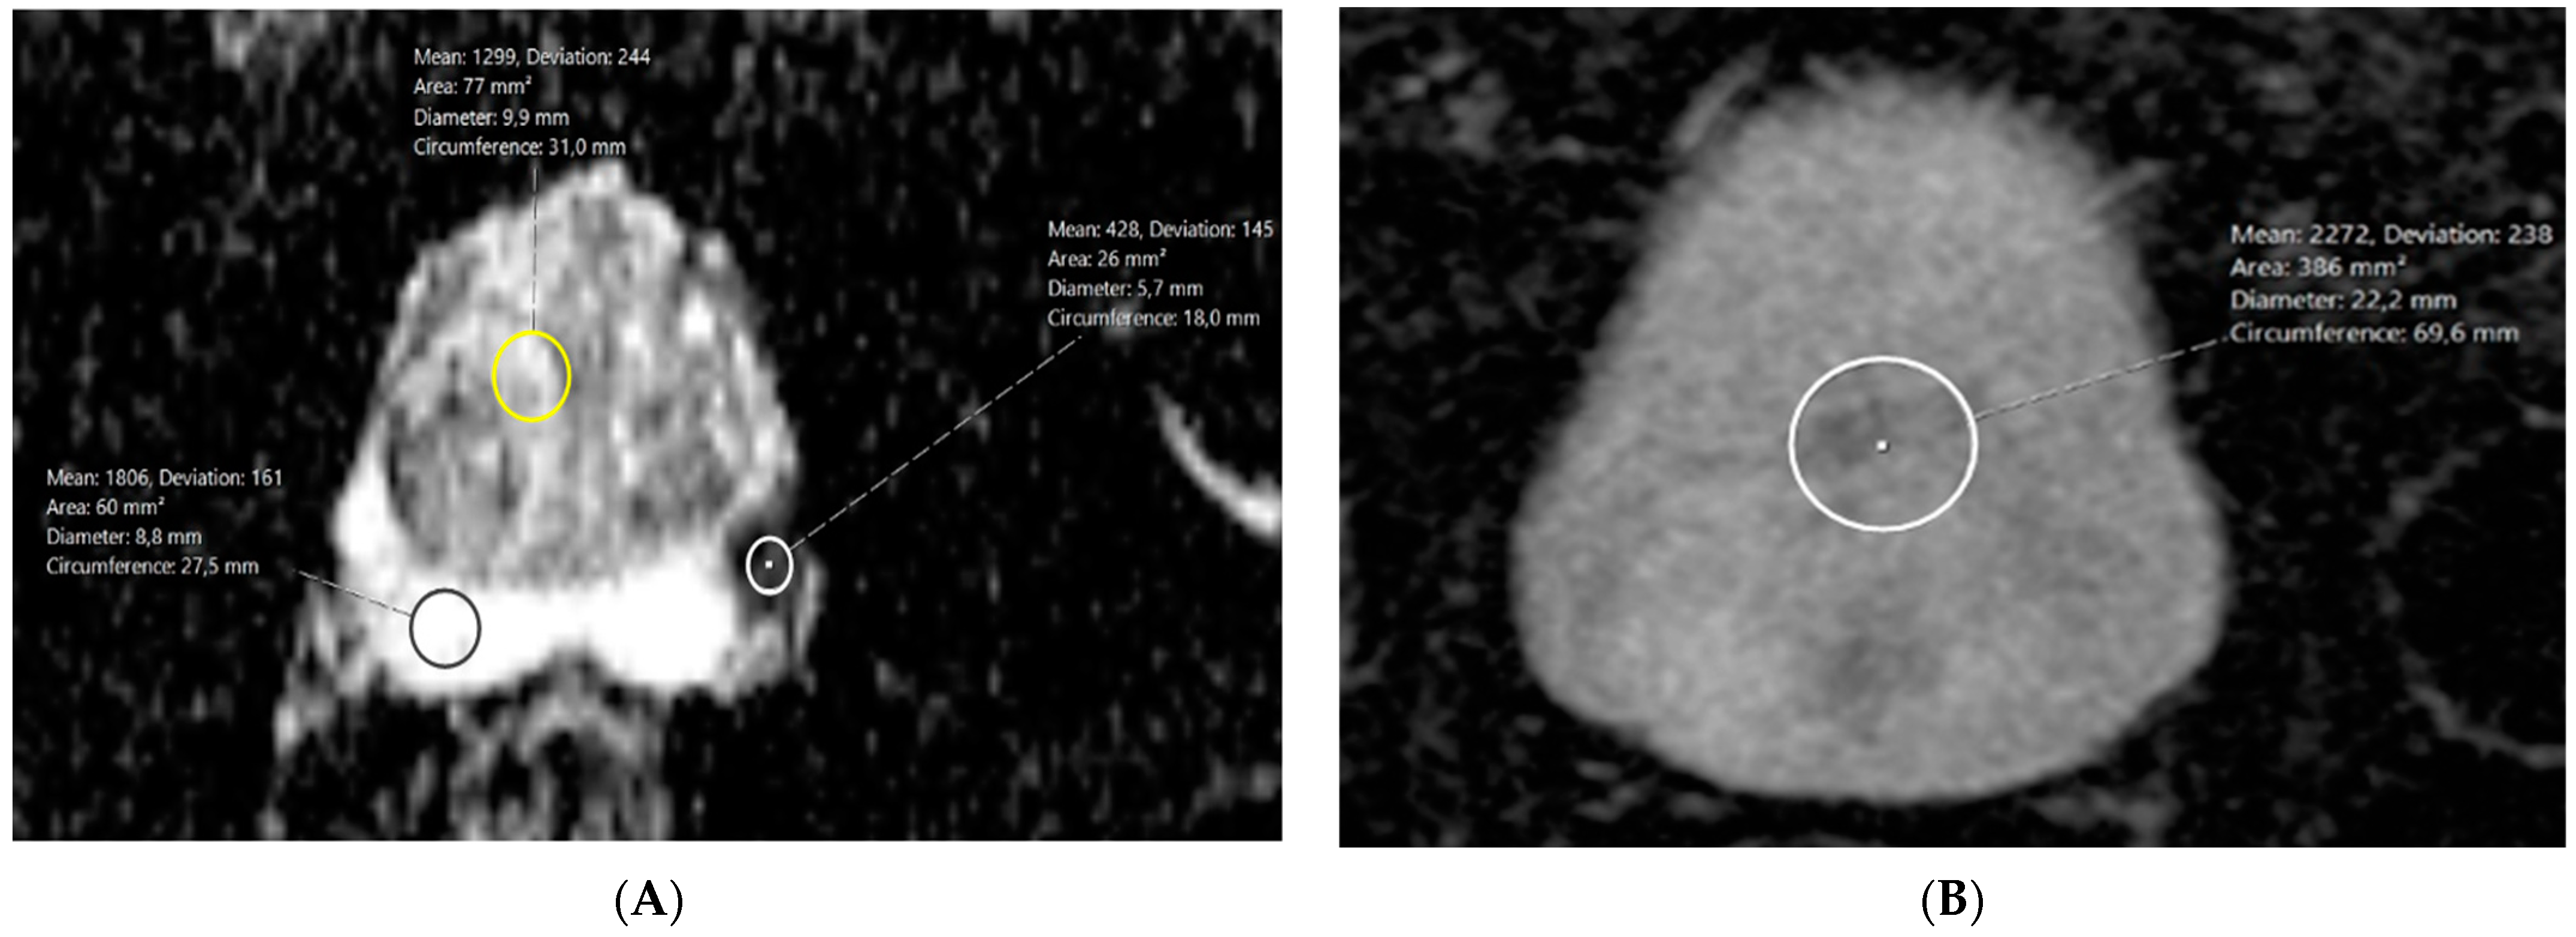

Figure 2 shows a representative case of a ROI placement in a 74-year-old patient, PSA 11.9 ng/mL, classified as PI-RADS 5 on MRI and GS 8 on histopathology from a surgical specimen.

(A) Circular ROIs drawn in tumor (white), non-cancerous transitional zone (yellow), and noncancerous peripheral zone (black). Tumor ADC = 428 µm2/s; TZ ADC = 1299; and PZ ADC = 1806. (B) Circular ROI drawn in homogenous area of urinary bladder on ADC map. Urinary bladder ADC = 2272 µm2/s.